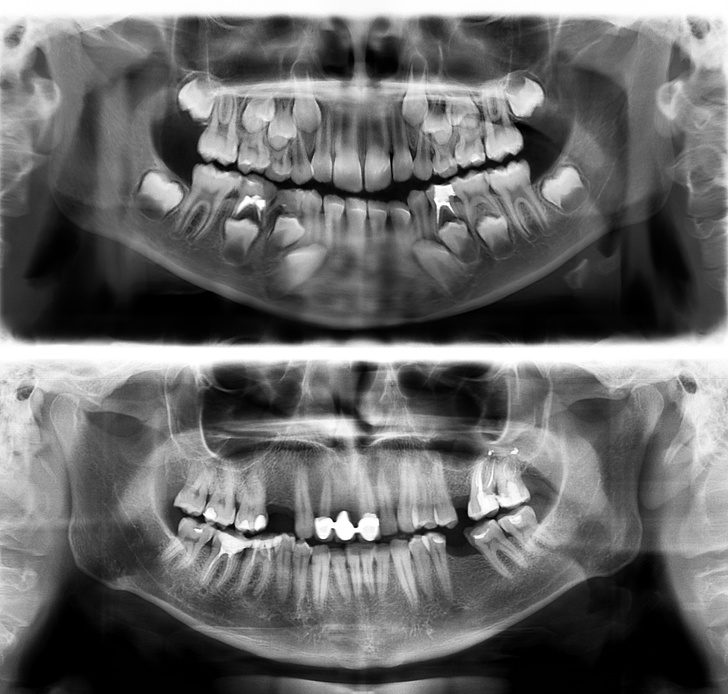

13. Так выглядят зубы человека в 7 (вверху) и в 30 лет